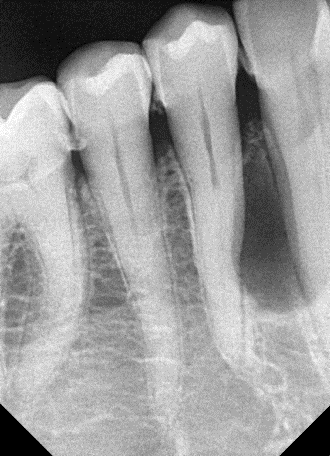

23. Select ONE correct answer.

What is the entity indicated by the arrow?